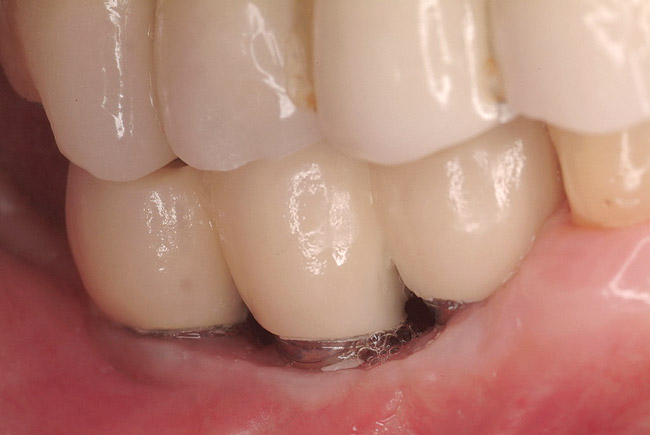

Figure 7  Final restoration of computer-guided implants.

Figure 7

A surgical guide, based on the 3-dimensional implant locations is fabricated for use in conjunction with the selected implant manufacturer's guided surgery instrumentation (Figure 4). Using this template, safe implant positioning in all three dimensions is performed, avoiding trauma to vital anatomic structures respecting the restorative outcome prescribed prior to surgery (Figure 5 and Figure 6). Following 8 weeks of transmucosal healing time, standard restorative therapy is initiated (Figure 7).